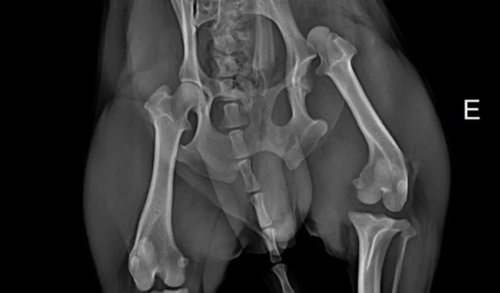

Graças a Deus ele sobreviveu mas sua partinha traseira saiu do lugar e teve alguns machucados.

Agora ele está se recuperando, porém teve de fazer vários exames e teve de passar por um cirurgia complicada para poder voltar sua patinha traseira ao lugar. Fora os medicamento que vai ter de tomar durante sua recuperação, que deve demorar na média de 3 meses para estar 100%.Precisamos muito da ajuda de vocês, com os gastos da cirurgia e dos exames.

Em anexo imagens do Thor e dos gastos.